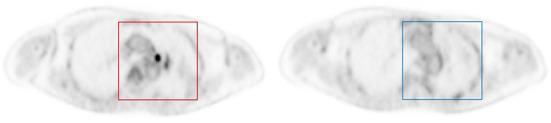

FDG PET imaging is often recommended for the diagnosis of pulmonary nodules after indeterminate low dose CT lung cancer screening. Lowering FDG injecting is desirable for PET imaging. In this work, we aimed to investigate the performance of a deep learning framework in the automatic diagnoses of pulmonary nodules at different count levels of PET imaging.

Twenty patients with 18F-FDG-avid pulmonary nodules were included and divided into independent training (60%), validation (20%), and test (20%) subsets. We trained a convolutional neural network (ResNet-50) on original DICOM images and used ImageNet pre-trained weight to fine-tune the model. Simulated low-dose PET images at the 9 count levels (20 × 10, 15 × 10, 10 × 10, 7.5 × 10, 5 × 10, 2 × 10, 1 × 10, 0.5 × 10, and 0.25 × 10 counts) were obtained by randomly discarding events in the PET list mode data for each subject. For the test dataset with 4 patients at the 9 count levels, 3,307 and 3,384 image patches were produced for lesion and background, respectively. The receiver-operator characteristic (ROC) curve of the proposed model under the different count levels with different lesion size groups were assessed and the areas under the ROC curve (AUC) were compared.